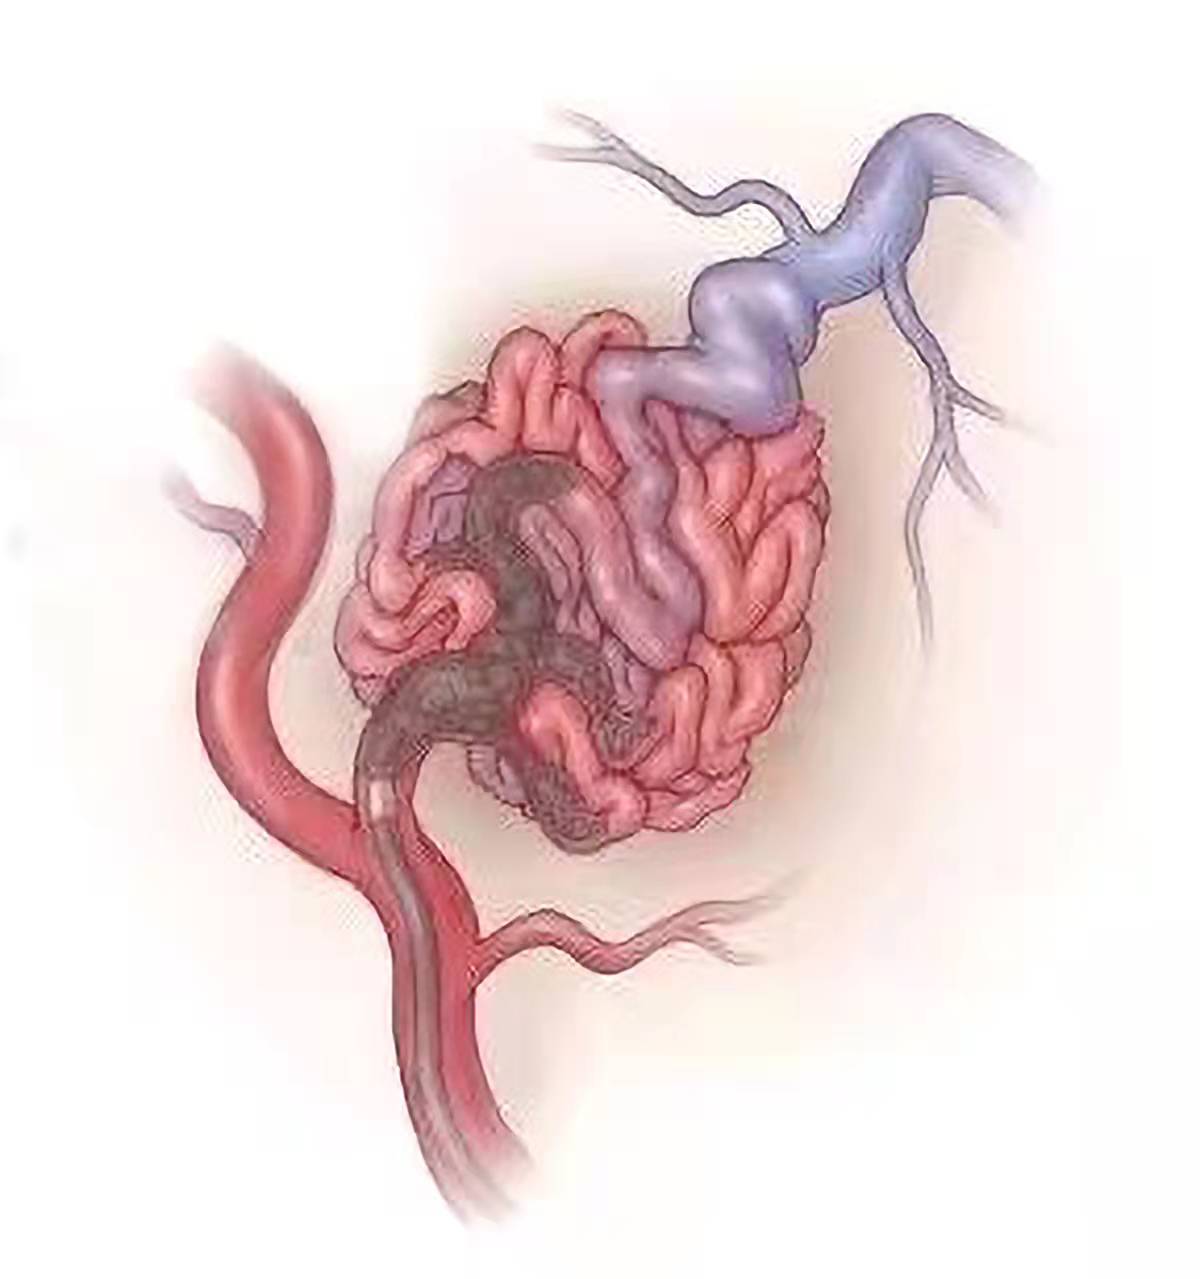

文章图片

△动静脉畸形栓塞术示意图

术中 , 凭借丰富的临床经验和娴熟的手术技巧 , 在神经电生理监测技术下 , 贾栋院长带领徐君副主任 , 使用微导管超选 , 采用液态栓塞系统 , 用导管将液体栓塞剂有控制地注入"大核桃"的供血动脉内 , 使之发生闭塞 , 中断血供 , 降低血流量 , 顺利将畸形血管团栓塞90%以上 , 引流静脉保留良好 , 脑血管得以重新布阵 , 脑血流得到良好的重新分布 。